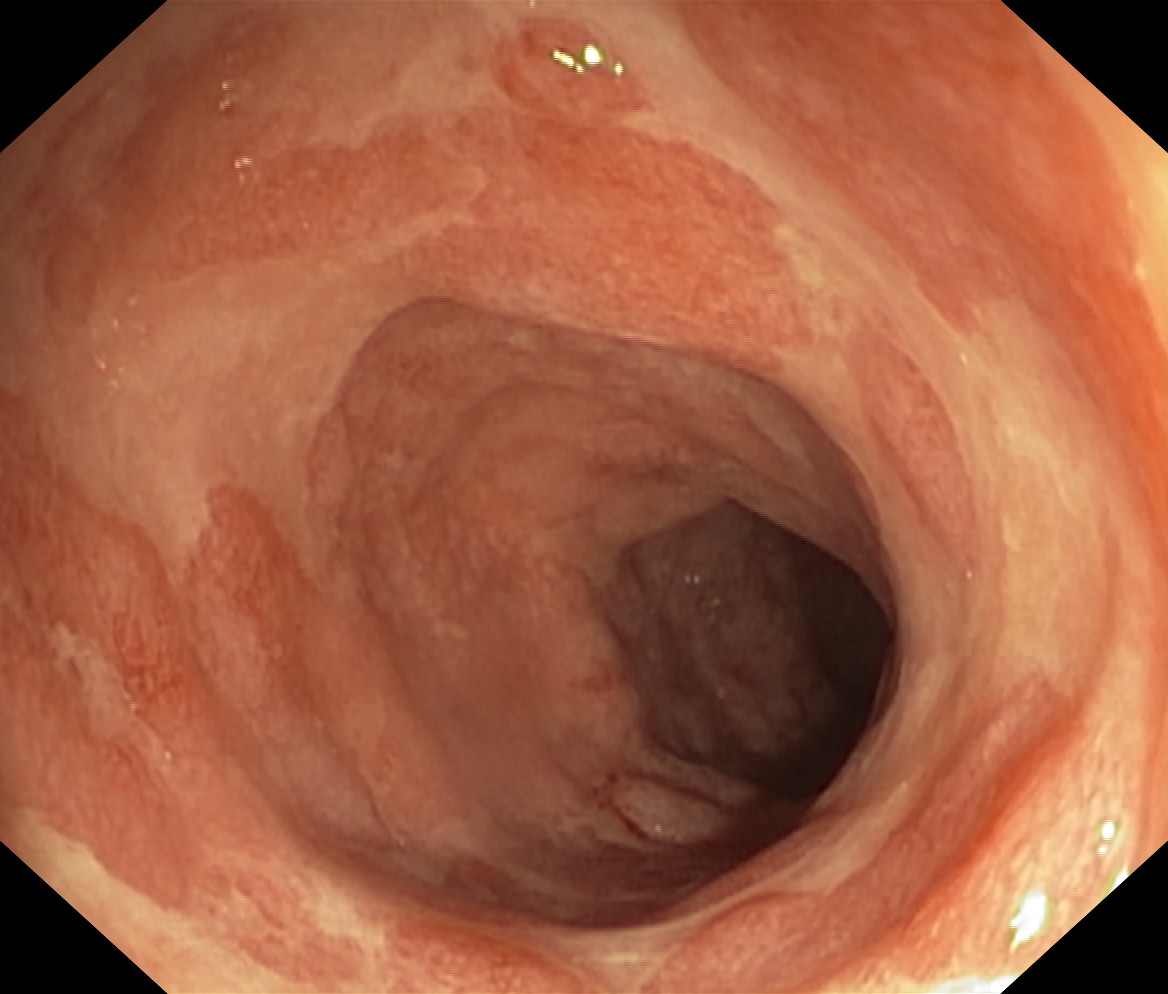

Zapalenie wrzodziejące...

Zapalenie wrzodziejące jelita grubego